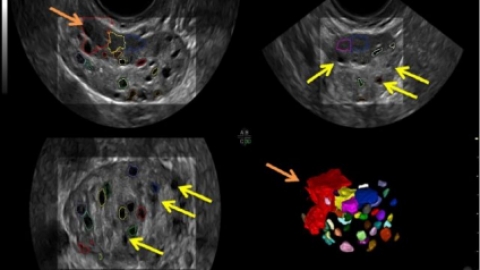

正常窦卵泡个数在5-10个之间,窦卵泡计数在生育与检测卵巢功能问题上是非常常用的,但是检测的结果可能并不都是那么尽人意的,很多女性在通过窦卵泡计数监测的出来的结果是5个、3个、11个等等,对于这样的结果通常都已经偏离了窦卵泡计数正常数量了,所以被认定为物偏少、偏多,而对于偏多将面临这多囊卵巢这一个女性妇科疾病。

那么你知道窦卵泡计数检查应在经期的第几天吗?而窦状卵泡就是女性朋友卵巢内休息卵泡,窦卵泡的数量和质量直接关系着女性是否成功受孕的关键,根据我们现在的医疗水平,观察评估卵泡的最好方式就是对女性朋友,进行阴道超声检查。因此窦卵泡与女性的年龄相关,与月经周期无明显相关,可在月经初期的时候较准确的被计数。

什么是窦卵泡?正常的情况下双侧卵巢是轮流排卵的,每个月会有一侧卵巢有一个成熟卵泡。在我们看来,随着女性年龄的增长,窦卵泡计数是迄今为止最好的工具,能帮助我们估计卵巢储备情况,药物刺激卵巢的响应,以及判断体外受精怀孕的成功率。窦状卵泡数量较少时,成熟卵泡的数量也会相应缩小,试管婴儿的成功怀孕率就会总体降低。